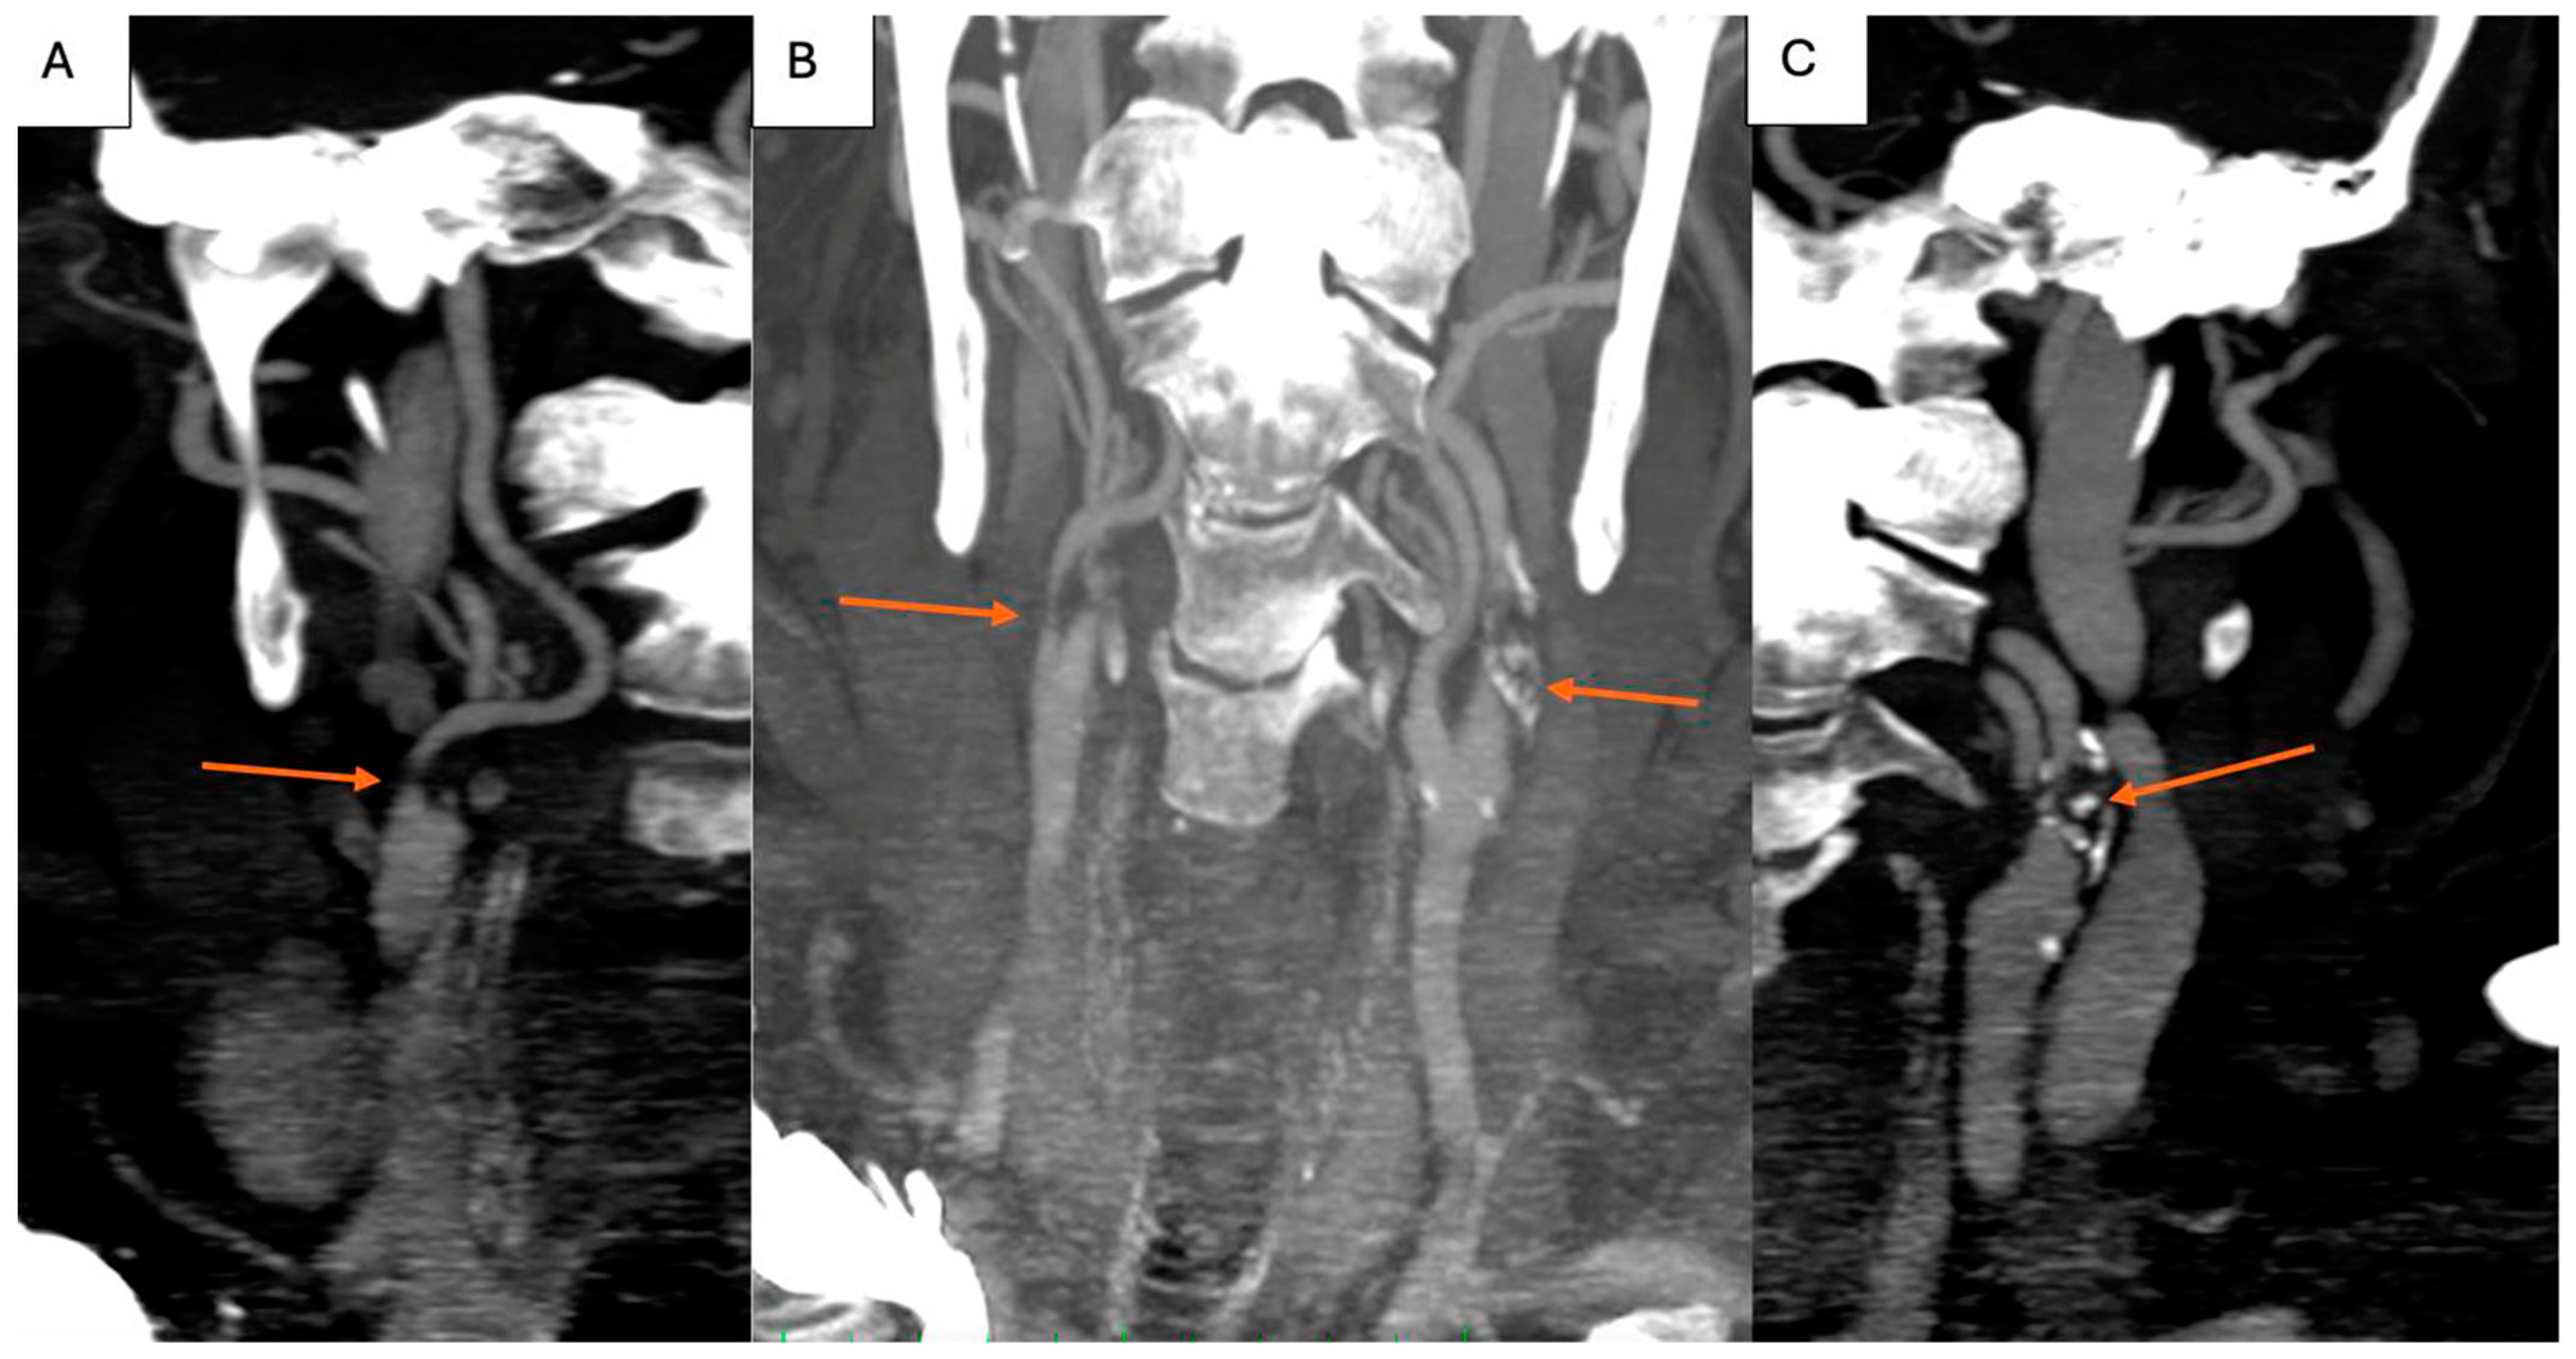

Cervical CT angiography confirmed the severe lesions at the level of the carotid arteries (Figure 2A–C). Additionally, considering the history of ischemic heart disease, coronary angiography was obtained, and carotid angiography was performed in the same setting. Figure 3 shows severe suboclusive stenosis at the level of the left common and internal carotid artery. Unfortunately, the cannulation of the right carotid artery was not possible. Coronary arteries were without any significant stenosis, and the stents at the level of the anterior descending artery were patent.

Figure 2.

Cervical CT angiography showing right severe internal carotid artery stenosis ((A), arrow), left severe internal carotid artery stenosis ((C), arrow), and bilateral severe internal carotid artery stenosis ((B), arrows).